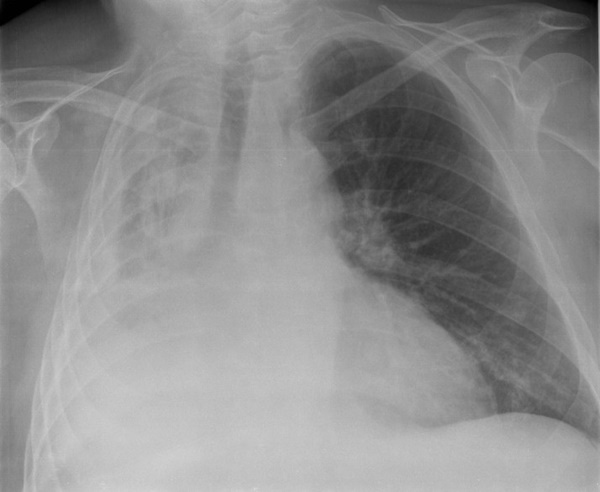

Phim X-quang của một người bị xẹp phổi

Xẹp phổi là tình trạng chèn ép hoặc tắc nghẽn phổi dẫn đến giảm hay mất khả năng trao đổi khí. Nó có thể ảnh hưởng đến một phần hoặc toàn bộ phổi. Đặc biệt, nó có thể xảy ra với cả trẻ em lẫn người cao tuổi. Cách nhanh nhất để phát hiện thường là chụp X-quang.